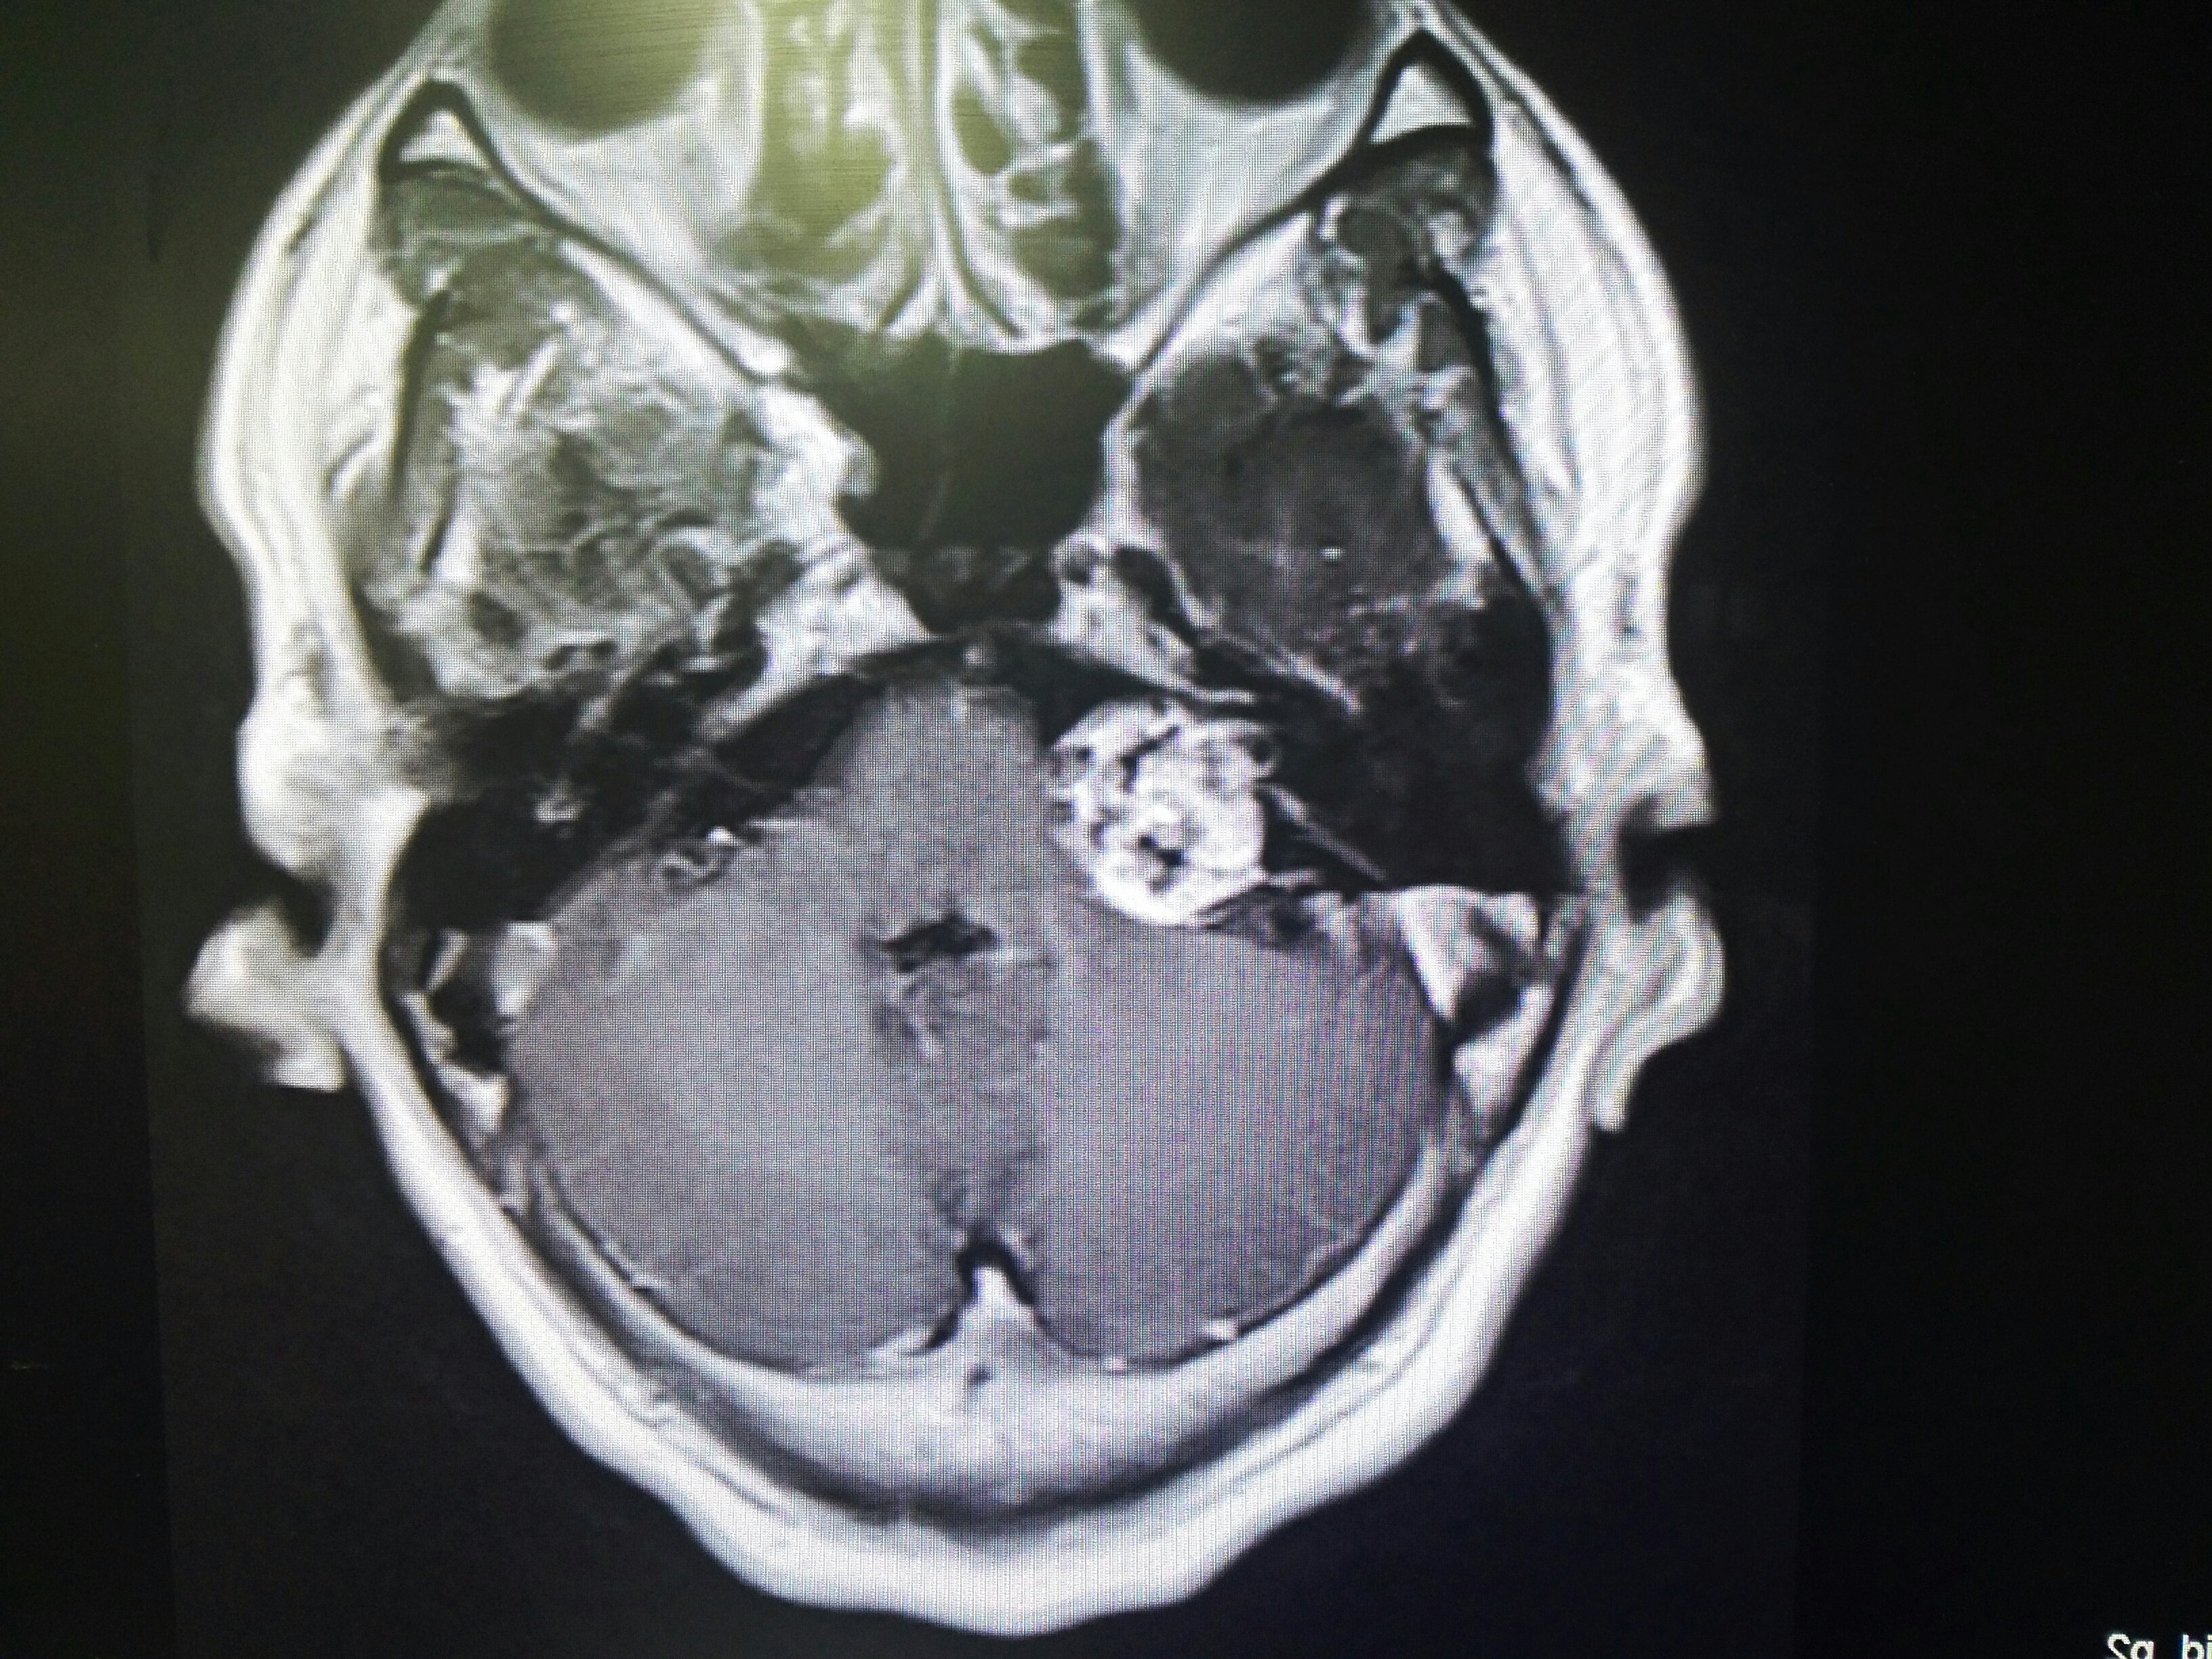

患者中年女性,2023年2月我院行行右側(cè)聽瘤切除術(shù),由于腫瘤巨大,術(shù)中面神經(jīng)有騷擾,術(shù)后出現(xiàn)輕度面神經(jīng)功能障礙,患者心理壓力較大。不過,術(shù)中電生理監(jiān)測一直顯示面神經(jīng)結(jié)構(gòu)完好,所以我十分有信心的告訴患者面神經(jīng)功能一定會回復(fù)。本次返院復(fù)查,患者的面神經(jīng)功能已經(jīng)完全恢復(fù),復(fù)查磁共振也顯示腫瘤切除滿意?;颊呗冻隽藵M意的笑容,可以開開心心的回家過年了。